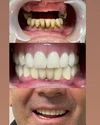

Zirconium Applications

Porcelain Applications

Laminate Veneer